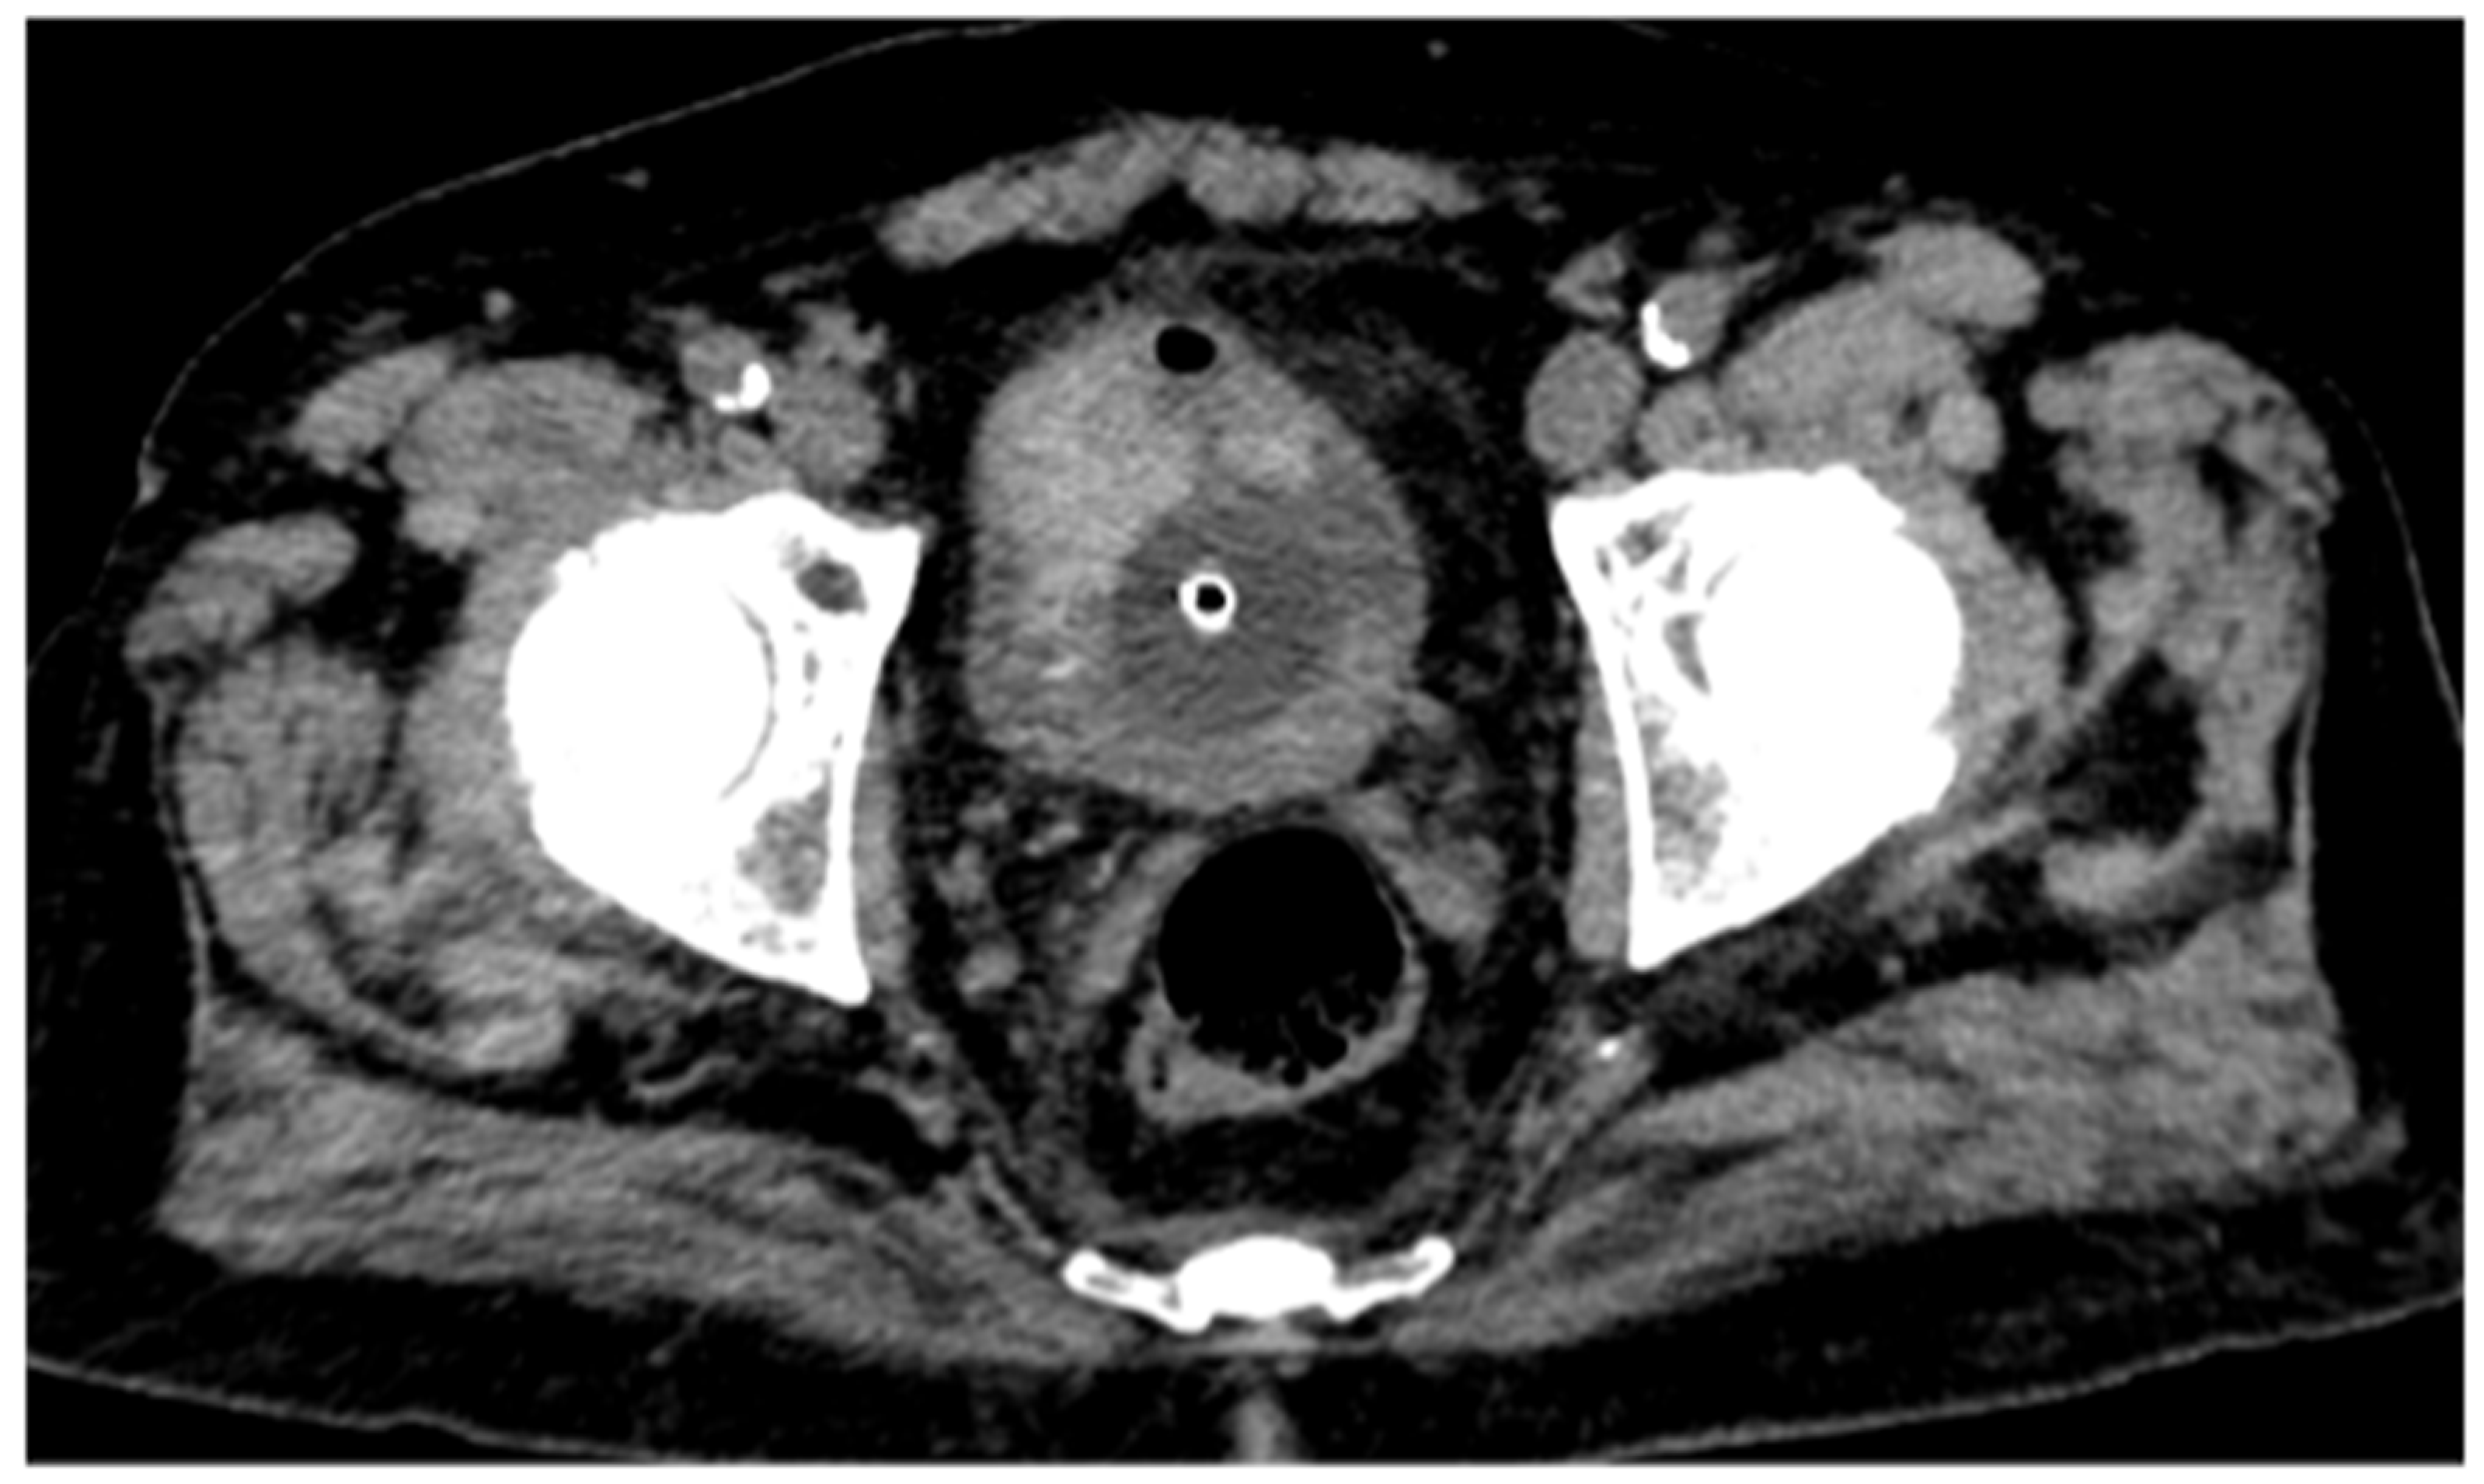

To further confirm the differing structural composition of the two tissue types, additional spectral maps were utilized. Specifically, the Z-effective map, based on the effective atomic number, combined with the electron density map, reflecting tissue electron composition, enabled a clear distinction between thrombotic and neoplastic tissue based on their unique physical properties (Figure 4).

Figure 4. Fusion of Z-effective and electron density maps from the non-enhanced scan demonstrates an endoluminal thrombus with its characteristic structural features.